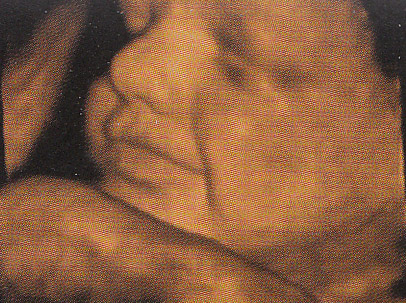

3D/4D Ultraschall